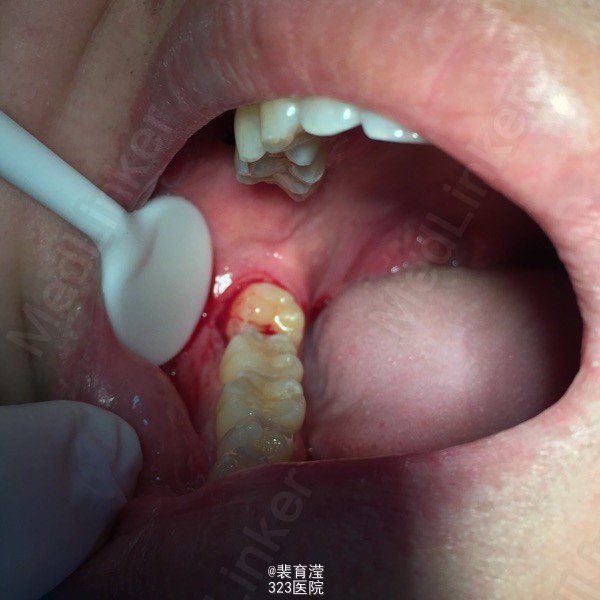

检查:右侧上颌第一磨牙,颊部前庭沟底,直径1.5mm 囊肿,探不适,波动感。 右下第三磨牙 近中阻生

诊断:异物囊肿 右下第三磨牙阻生 处理:1.局麻下切除异物囊肿,缝合,止血。 2.右下第三磨牙局麻下 拔除 搔刮牙槽窝 止血。